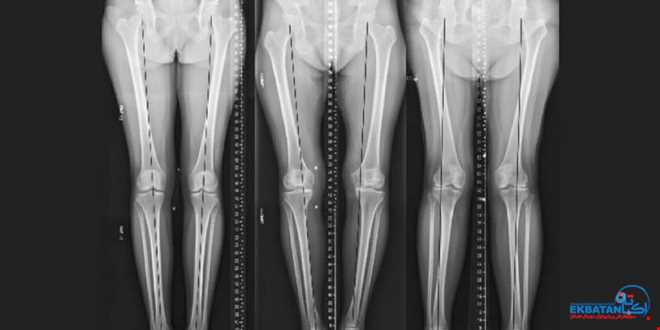

رادیوگرافی الاینمنت یا تری جوینت ویو، تصویربرداری تخصصی است که محور مکانیکی کل اندام تحتانی را از لگن تا مچ پا بررسی می‌کند. در این روش سه مفصل اصلی:

مفصل ران (Hip)

مفصل زانو (Knee)

مفصل مچ پا (Ankle)

همزمان و در وضعیت ایستاده (Weight bearing) ثبت می‌شوند. این تصویر، امکان مشاهده و اندازه‌گیری دقیق زاویه‌ها و انحرافات محور پا را فراهم کرده و رابطه آن با فشار وارد بر مفصل زانو را روشن می‌سازد.